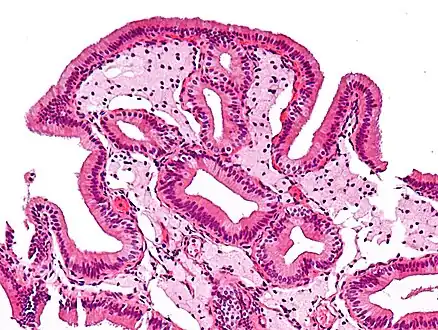

| Micrograph of cholesterolosis of the gallbladder, a very common gallbladder disease. Cholecystectomy specimen. H&E stain. | |